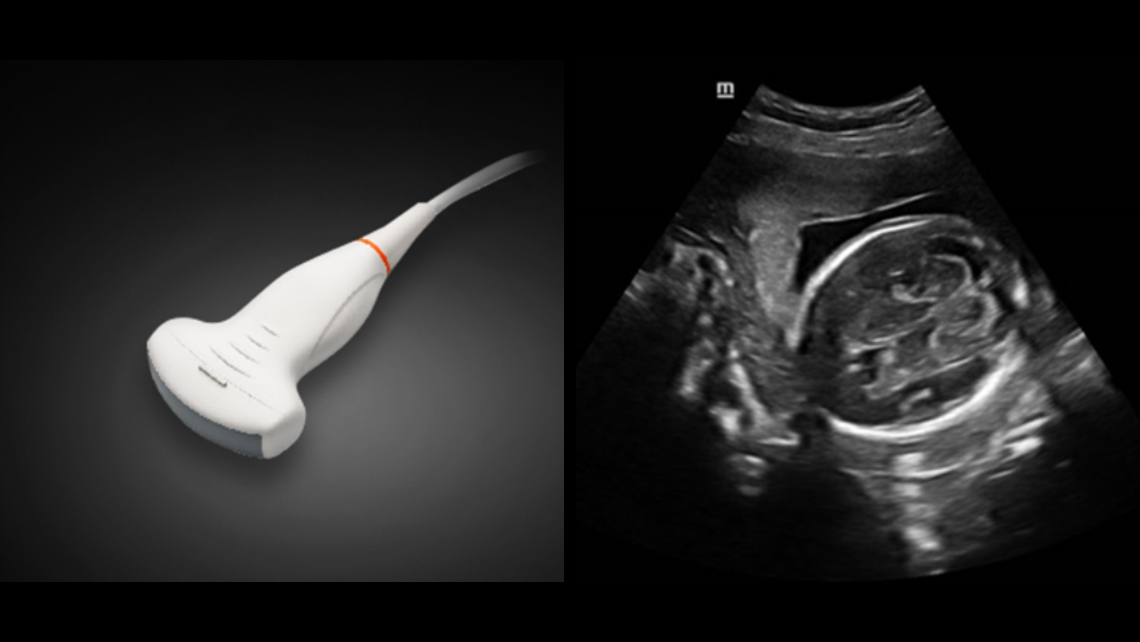

SoluciĂłn de volumen doble DE11-3E

SC5-1N y SD8-1E

SoluciĂłn de volumen doble DE11-3E

SC5-1N y SD8-1E

ImĂĄgenes clĂnicas